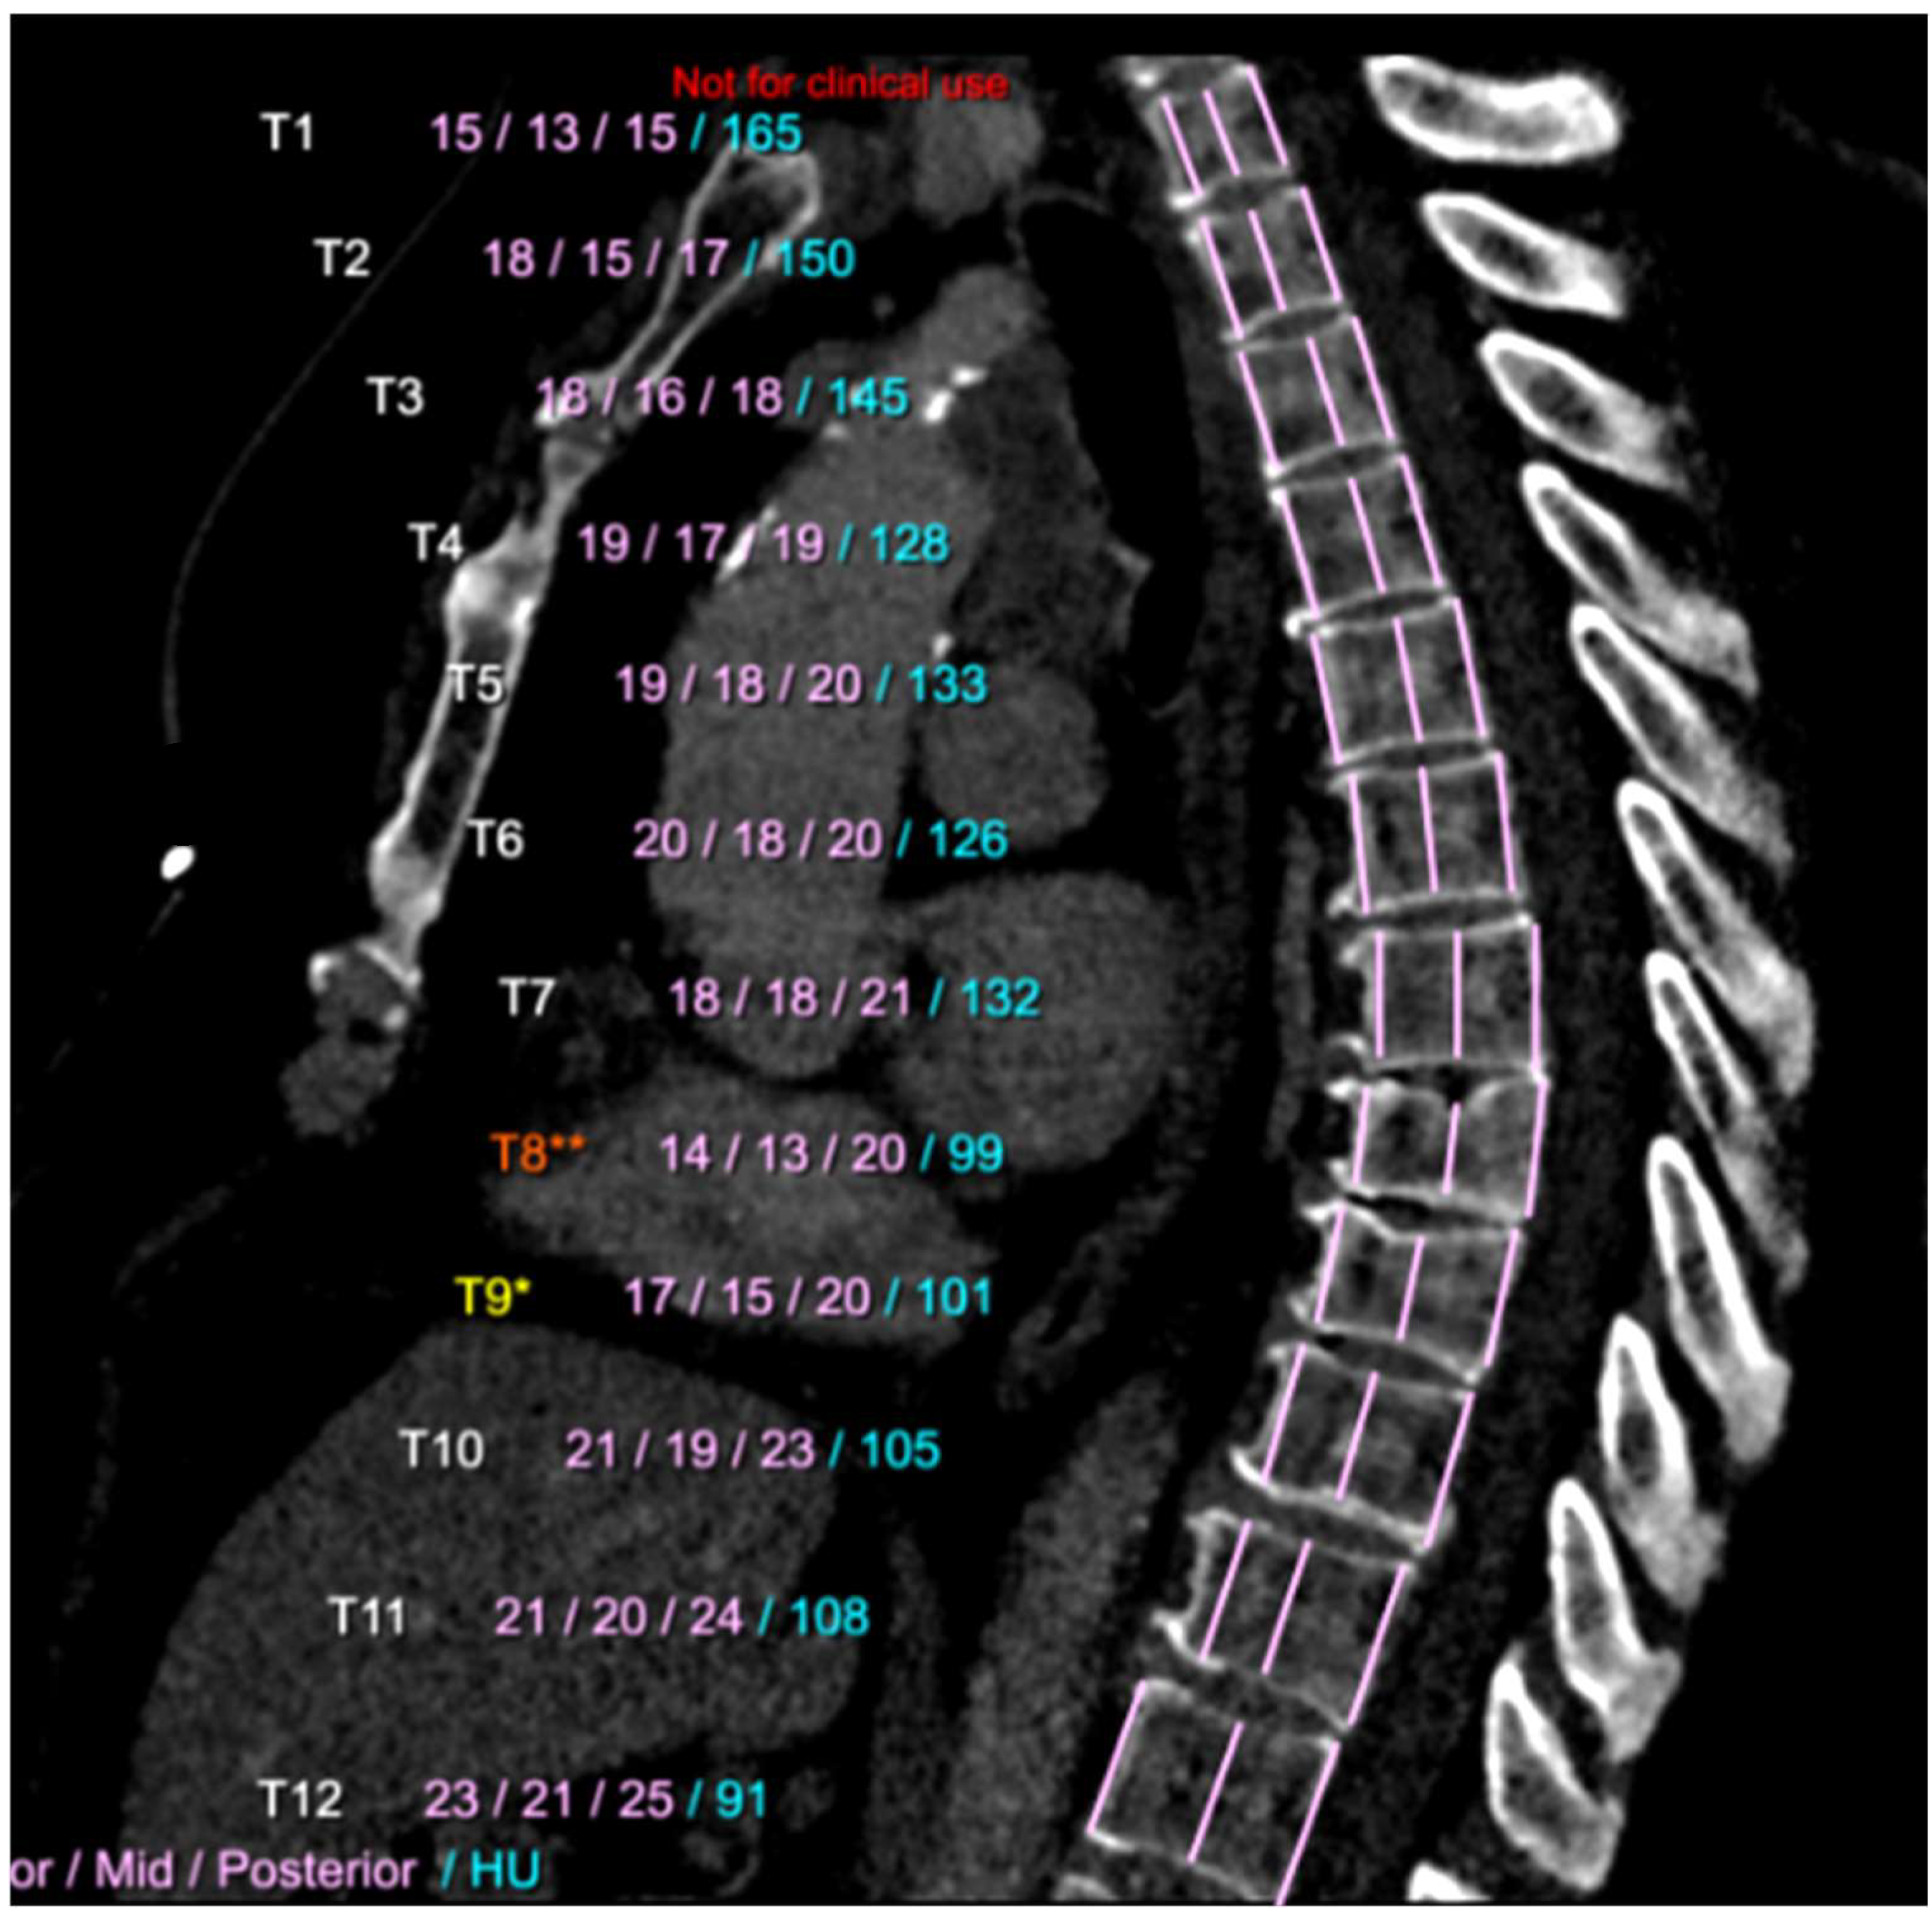

3.3. Osteoporosis and Fragility Fractures

- Van Dort, M.J.; Driessen, J.H.M.; Geusens, P.; Romme, E.A.P.M.; Smeenk, F.W.J.M.; Wouters, E.F.M.; van den Bergh, J.P.W. Vertebral bone attenuation in Hounsfield Units and prevalent vertebral fractures are associated with the short-term risk of vertebral fractures in current and ex-smokers with and without COPD: A 3-year chest CT follow-up study. Osteoporos. Int. 2019, 30, 1561–1571. [Google Scholar] [CrossRef] [PubMed]

- Fang, Y.; Li, W.; Chen, X.; Chen, K.; Kang, H.; Yu, P.; Zhang, R.; Liao, J.; Hong, G.; Li, S. Opportunistic osteoporosis screening in multi-detector CT images using deep convolutional neural networks. Eur. Radiol. 2021, 31, 1831–1842. [Google Scholar] [CrossRef] [PubMed]

- Pan, Y.; Shi, D.; Wang, H.; Chen, T.; Cui, D.; Cheng, X.; Lu, Y. Automatic opportunistic osteoporosis screening using low-dose chest computed tomography scans obtained for lung cancer screening. Eur. Radiol. 2020, 30, 4107–4116. [Google Scholar] [CrossRef] [PubMed]